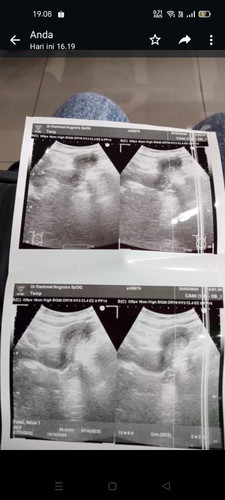

SDH USG tp blm kelihatan.udh 2 bulan nda haid . Tp diksh vitamin disuruh balik 1 bulan lg

udah 2 bulan ga haid masuknya 8w lebih kalo nunggu sebulan lg berarti 12w lebih lebih baik second opini,pindah dokter bun, ko saya bingung yaa 8w minimal udah keliatan kantung kehamilan 10w keliatan embrio

Sudah usg tranvsaginal bun? Coba gnti dokter atau lainnya krn lumayan lama 2 bulan dan bunda blg biasanya teratur

Lebih baik usg transvaginal bunda

coba USG transvaginal bund